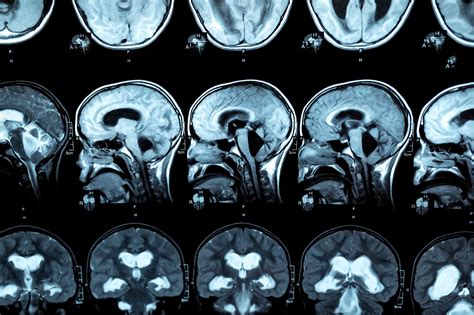

Nedávna štúdia Lekárskej univerzity vo Viedni (Medizinische Universität Wien), ktorú vedci prezentovali na minuloročnom výročnom stretnutí Rádiologickej spoločnosti Severnej Ameriky, poukázala na nepriaznivé účinky alkoholu v prenatálnom období. Vedecký tím z Lekárskej univerzity vo Viedni preto uskutočnil štúdiu, ktorej cieľom bolo zistiť vplyv alkoholu na štruktúry mozgu u nenarodených detí a zároveň „aktívne vzdelávať verejnosť o účinkoch alkoholu na plod“. Na štúdii sa zúčastnilo 24 budúcich matiek, ktoré boli v 22. až 36. týždni tehotenstva.

„Fetálna magnetická rezonancia je vysokošpecializovaná a bezpečná vyšetrovacia metóda, vďaka ktorej vieme získať presný obraz o dozrievaní mozgu v prenatálnom období,“ uviedol neurorádiológ Gregor Kasprian, hlavný autor štúdie. Tím vedcov porovnal získané výsledky s výsledkami plodov budúcich matiek, ktoré počas tehotenstva alkohol nekonzumovali. Výsledky ukázali, že v prípade plodov vystavených alkoholu bol vývoj oneskorený, čo sa oproti druhej kontrolnej skupine prejavilo v nízkom celkovom skóre dozrievania plodu (Fetal Total Maturation Score). Okrem toho mali slabšie vyvinutú oblasť mozgu zodpovednú za vývoj sociálnej a rečovej oblasti, tzv. sulcus temporalis superior (STS). Neurorádiológ Gregor Kasprian poukázal na veľký vplyv „STS na vývoj rečových schopností v detstve“.

Zmeny v mozgových štruktúrach sa pritom zistili aj v prípade plodov žien, ktoré konzumovali alkohol len sporadicky. Podľa autora štúdie Patrica Kienasta požívalo 17 z 24 budúcich matiek alkohol veľmi nepravidelne, v priemere si dali menej ako jeden pohárik týždenne. „Napriek tomu sme aj v prípade plodov týchto matiek vyšetrením MRI zistili signifikantné zmeny,“ uviedol Kienast. Tri probandky si dali jeden až tri poháriky, dve z nich štyri až šesť pohárikov týždenne. Jedna budúca matka dokonca uviedla, že týždenne skonzumuje 14 a viac pohárikov alkoholu.

Podľa vedcov môže konzumácia alkoholu v tehotenstve ovplyvniť najmä procesy myelinizácie a gyrifikácie. Ide o dôležité vývojové stupne v mozgu a nervovom systéme. Myelinizácia je úzko prepojená s procesmi učenia sa u dieťaťa, napríklad pri pretáčaní sa, lození a rozprávaní. Pod pojem gyrifikácie zasa spadá vytváranie mozgových závitov, tzv. gyrov. U človeka sa začína v 22. týždni. S gyrifikáciou súvisí mnoho kognitívnych procesov. Ako sa alkohol, ktorému boli plody probandiek vystavené v prenatálnom období, podpíše na vývoji budúcich detí, sa dá zistiť len ďalšou štúdiou.